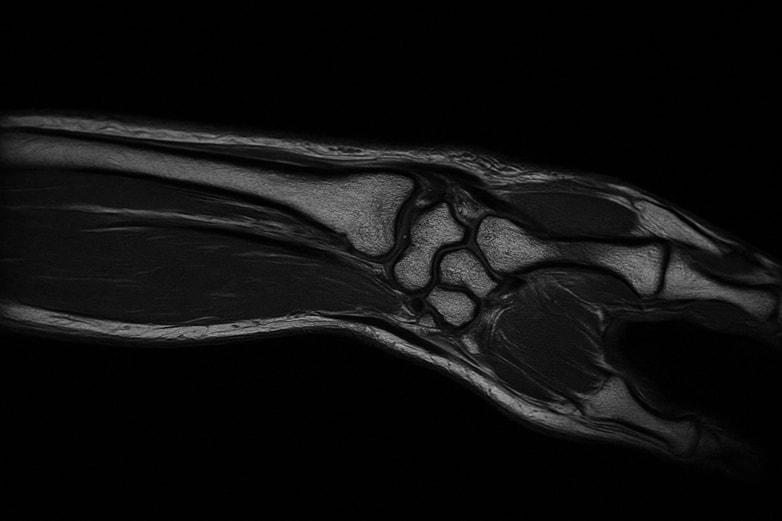

Магнитно-резонансная томография лучезапястного сустава дает возможность оценить состояние костей, хрящей, сосудов, нервов и мягкотканных структур, увидеть нарушения, которые невозможно зафиксировать другими способами. С помощью процедуры врач визуализирует микроскопические изменения в сухожилиях, суставах, связках и мышцах.

Аппарат создает серию послойных снимков, на которых видны мягкие ткани, сухожилия и кости запястья в мельчайших деталях. Важно сохранять неподвижность — от этого зависит качество визуализации.

После завершения сканирования врач лучевой диагностики изучает полученные изображения и составляет заключение. На снимках видны все анатомические элементы — от суставных поверхностей до микроструктуры мягкотканных структур и сухожилий.